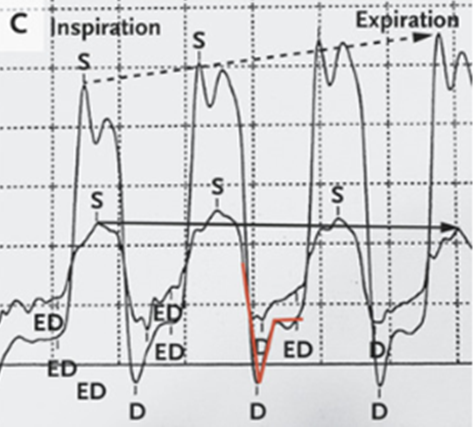

その後両心カテーテル検査が施行された。心室の相互依存性と圧力とレースの不一致が示された。

吸気中、右心室の圧が最も高くなる時、左心室の圧力が最も低くなっていた。

また拡張期初期の早急な心室充満を表す「平方根徴候(ディップ&プラトーパターンとも呼ばれる))」が見られた(赤線)。